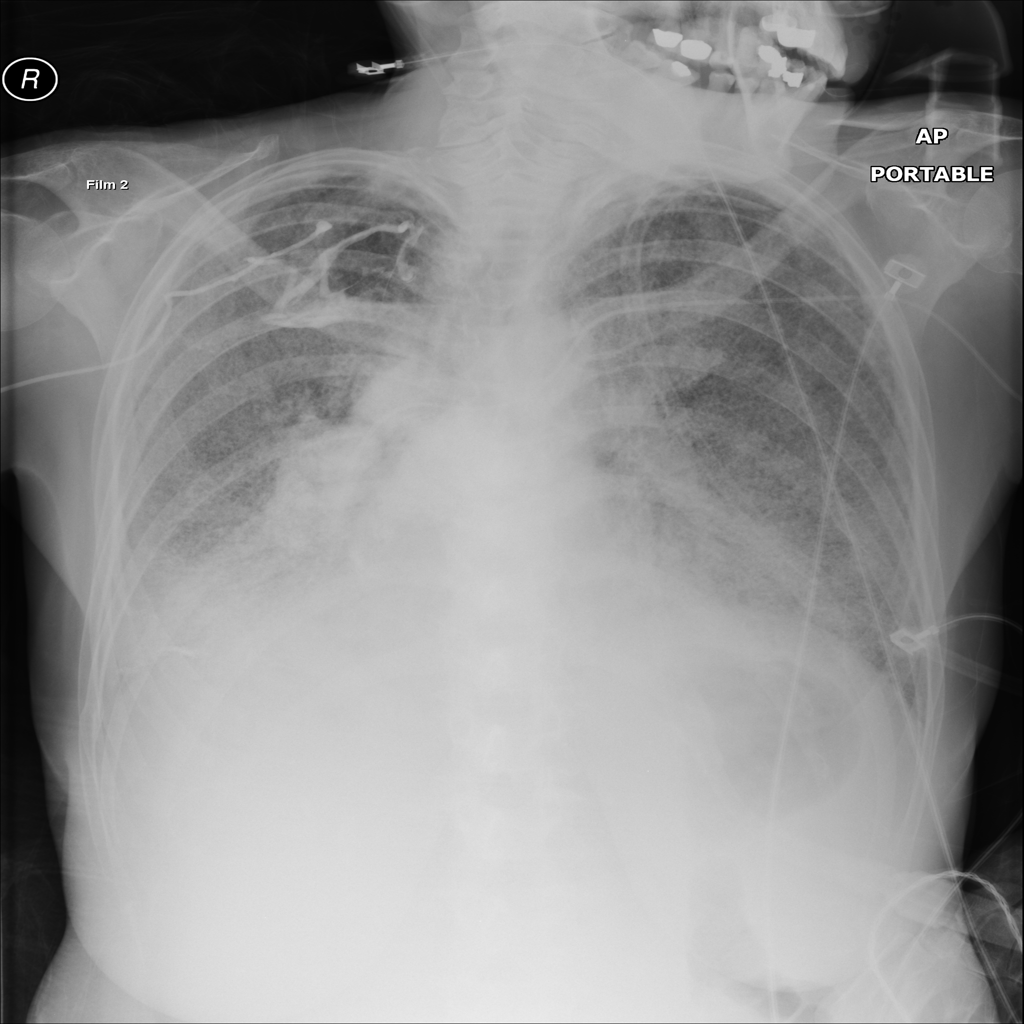

Mass

A mass is a larger focal opacity or lesion seen on the image. It is a descriptive finding that can have several causes and usually needs more imaging or clinical context to characterize.

PAT-BBAD · IMG-009Mass

PAT-BBAD · IMG-009

AP